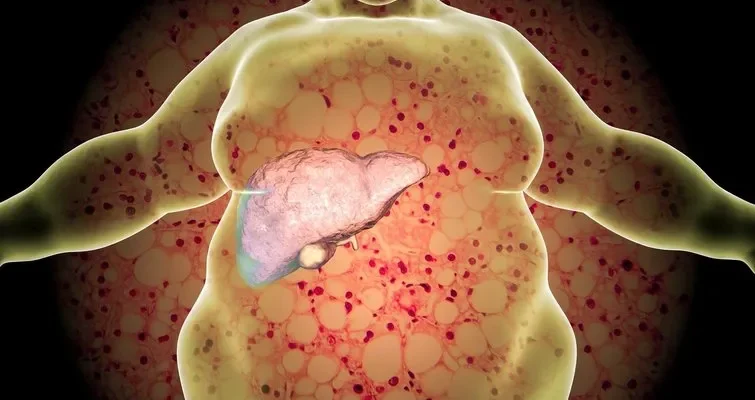

Suriebėjusios kepenys, remiantis Nacionaline sveikatos misija (NHM), yra būklė, kai kepenų ląstelėse kaupiasi riebalų perteklius, rašoma timesofindia.com.

Ji dažnai atsiranda dėl nutukimo, atsparumo insulinui ar medžiagų apykaitos sutrikimų ir negydoma gali sukelti kepenų uždegimą, pažeidimą ir rimtas komplikacijas.

Pilvo riebalų koncentracija

Turbūt labiausiai paplitęs suriebėjusių kepenų požymis yra didesnis riebalų kiekis pilvo srityje. Net ir žmonėms, kurie nėra pernelyg nutukę, per didelis pilvo riebalų kiekis yra įspėjamasis ženklas.

Šis centrinis nutukimas gali būti prastos kepenų funkcijos požymis ir dažniausiai pasireiškia atsparumu insulinui. Svorio valdymas laikantis dietos ir mankštinantis yra labai svarbus prevencijai.